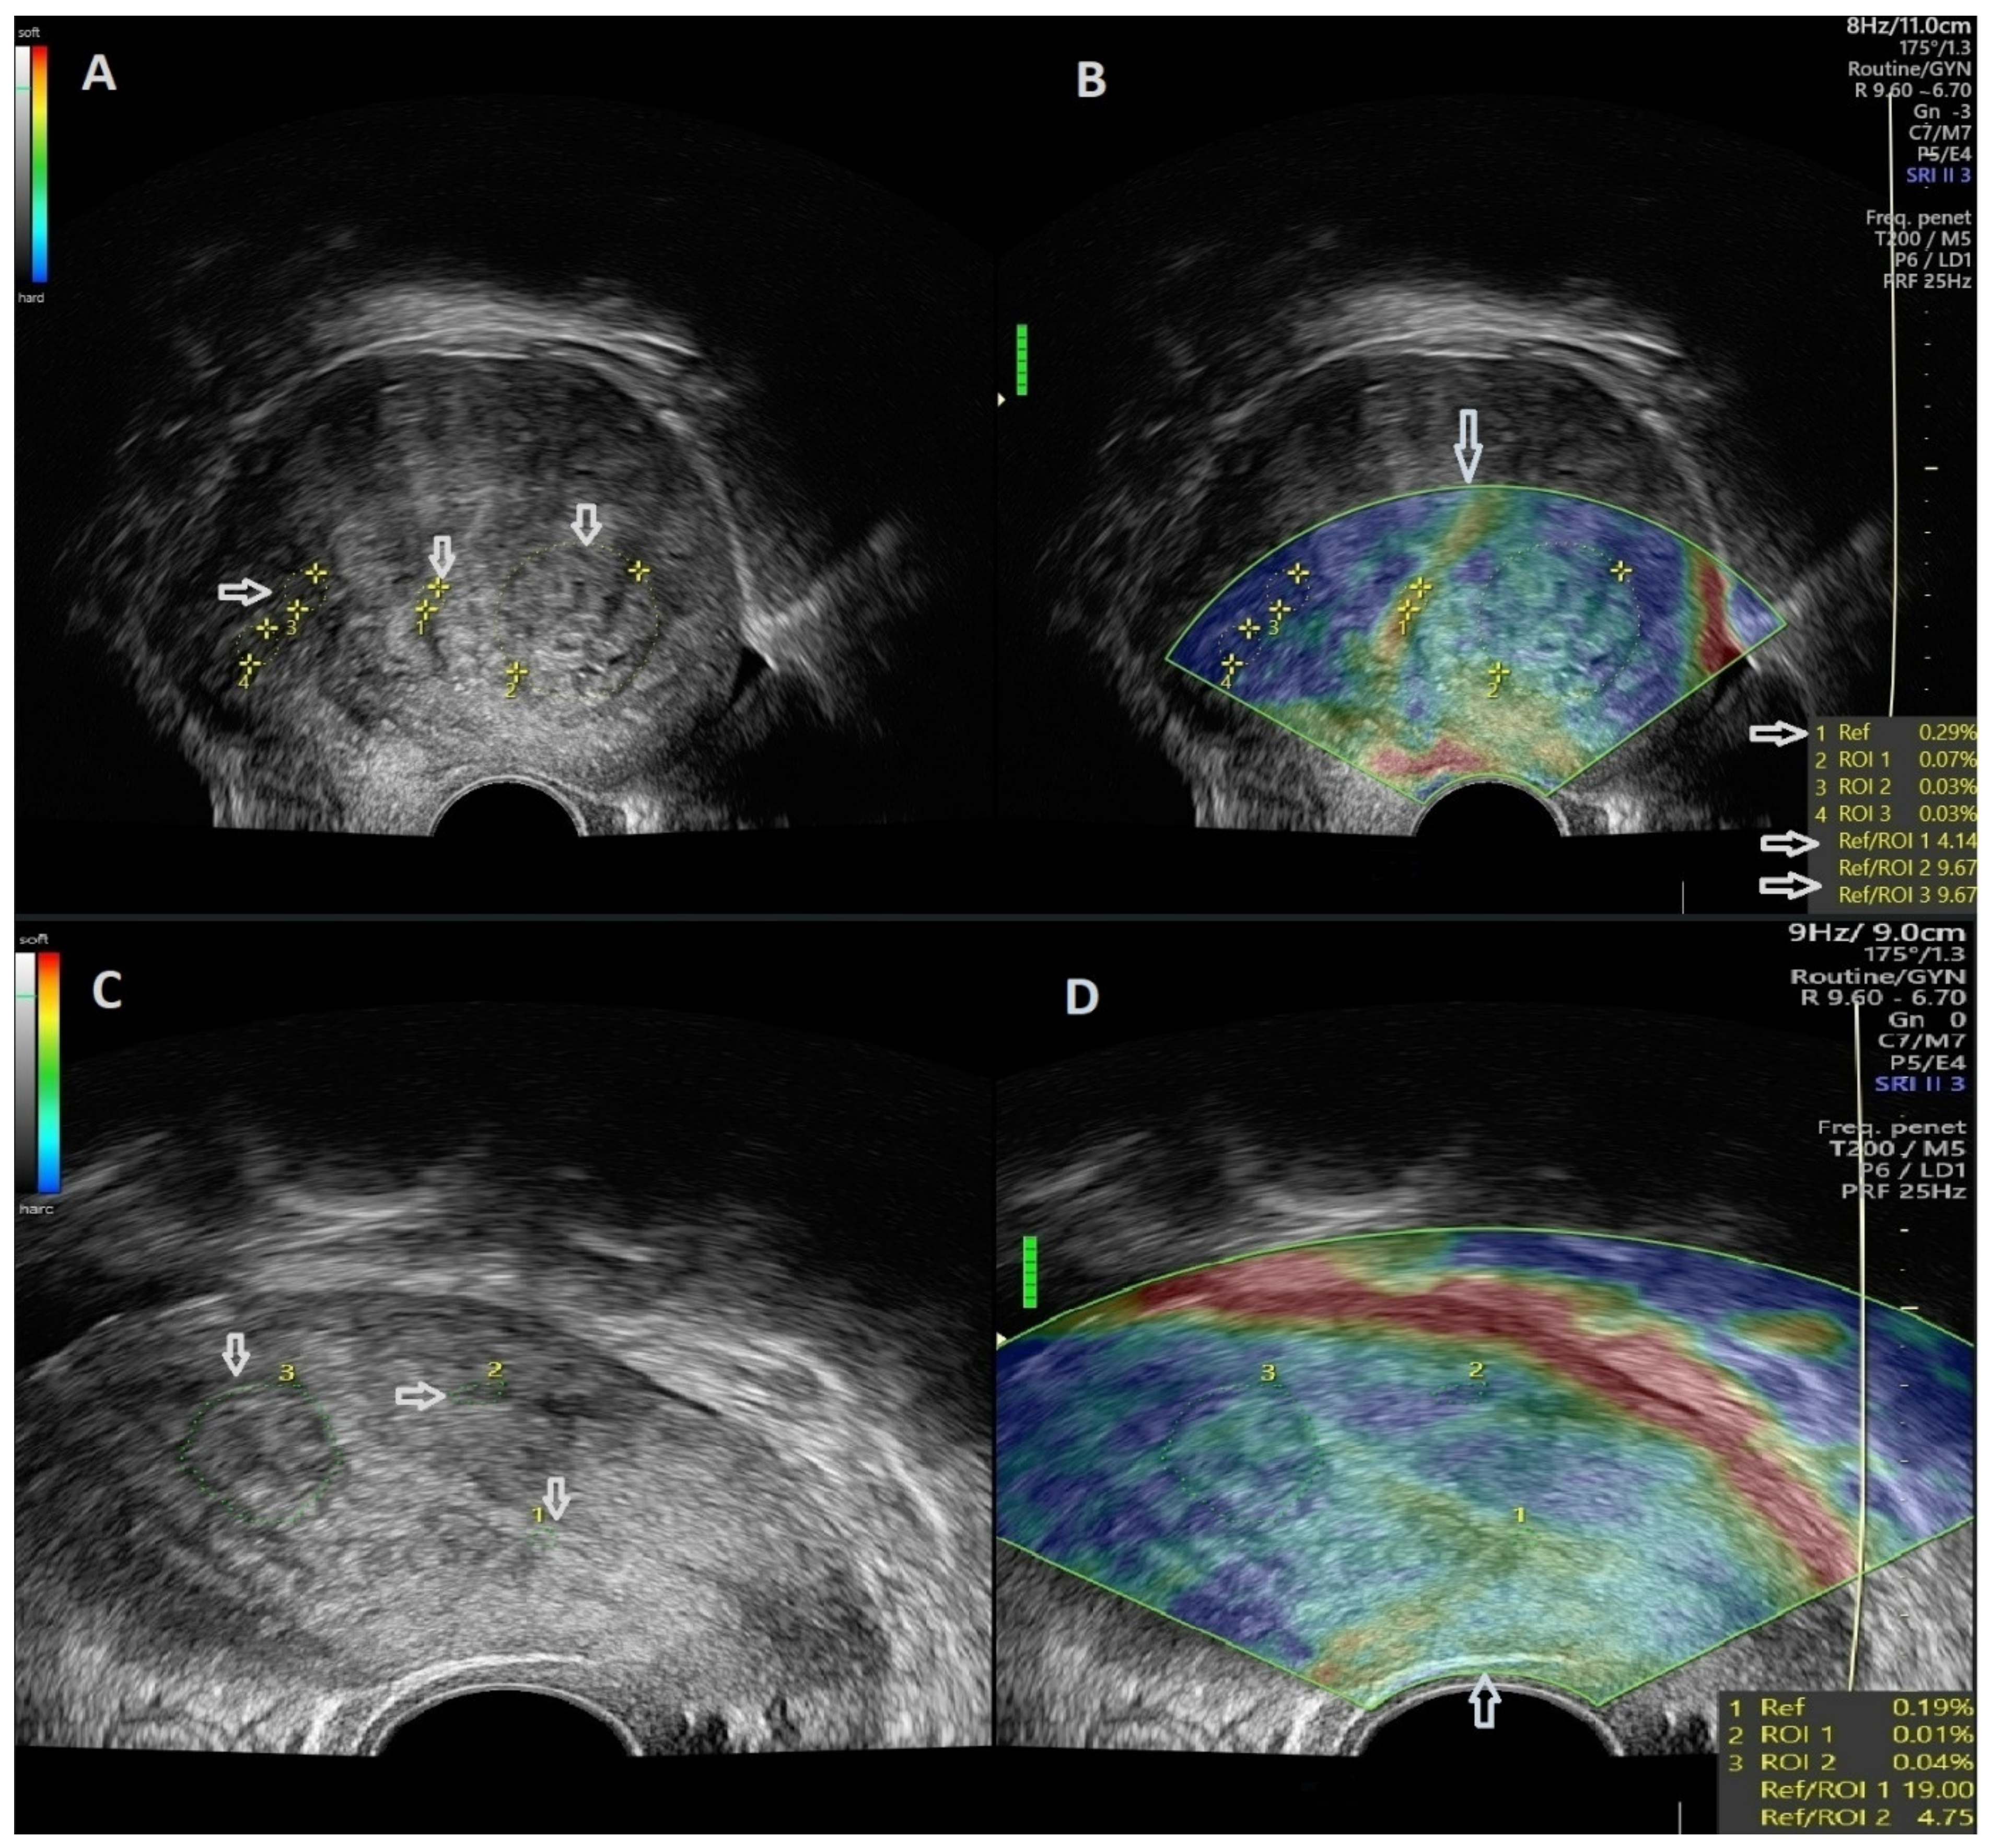

2.4. Strain Ratio Elastography Evaluation